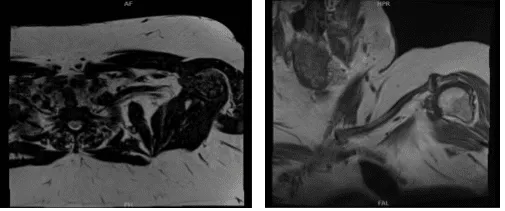

Se ha realizado una resonancia magnética de la clavícula y se ha presentado en la consulta. Acromion y bursa: El acromion tiene una configuración curva (tipo II). En la articulación acromioclavicular hay cambios degenerativos moderados. Una pequeña cantidad de líquido está presente en la bursa subacromial/subdeltoide.

Tendones del manguito rotador: Tendinosis supraespinosa presenta desgarros articulares de alto grado parcial y un componente de grosor total que afecta a los 2,2 cm anteriores del tendón supraespinoso distal.

La tendinosis infraespinosa está presente con desgarros articulares de alto grado parcial y espesor. También está presente tendinosis subescapular con desgarros parciales en su inserción. Tendones del bíceps: No se visualiza la cabeza larga del tendón del bíceps, lo cual es compatible con una rotura completa y una retracción distal.

Cartílago y labrum: Hay irregularidad superficial del cartílago en la articulación glenohumeral. Está presente desgarro degenerativo del labrum glenoideo posterosuperior. Médula ósea:

La formación de quistes subcondrales está presente en la parte posterior de la mayor tuberosidad. La señal de la médula ósea es en general adecuada para su edad.

No hay evidencia de linfadenopatía significativa en las partes visualizadas de la axila. No hay atrofia asimétrica del manguito rotador. Decidimos hacerle otra resonancia magnética para hacer más pruebas de su hombro.

Primer resultado de la resonancia magnética

Segundo resultado de la resonancia magnética